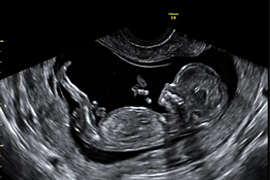

Schon gegen Ende des ersten Schwangerschaftsdrittels sind alle kindlichen Organe angelegt. Auch wenn Sie keine Untersuchung zur Vorhersage des Risikos für eine genetische Veränderung (I. Trimesterscreening s.o.) wünschen, ist eine frühe Darstellung der Organe des Embryos sinnvoll, da hier schon viele schwere Entwicklungsstörungen ausgeschlossen werden können.

Zum jetzigen Zeitpunkt können bereits Gehirn, Herz, Zwerchfell, Magen, Bauchwand und Harntrakt sowie die Kopfkontur und die Extremitäten dargestellt werden. Einen „großen Ultraschall“ im 2. Drittel der Schwangerschaft kann diese Untersuchung allerdings noch nicht ersetzen.

Im zweiten Drittel der Schwangerschaft wächst das Kind und die Organe reifen weiter, um schließlich zum Zeitpunkt der Geburt ihre Funktion übernehmen zu können. Bei diesem Reifungsprozess verändert sich nur noch die mikroskopisch erkennbare Feinstruktur der meisten Organe. Die im Ultraschall darstellbaren typischen Organstrukturen sind jetzt schon vorhanden. Nur das Gehirn wird sich in den folgenden Wochen noch bedeutsam verändern.

Daher ist das zweite Drittel der Schwangerschaft ein geeigneter Zeitpunkt, eine differenzierte Ultraschallfeindiagnostik vorzunehmen. Das Kind schwimmt in reichlich Fruchtwasser – ein guter Schall-Leiter!

In der 20. Schwangerschaftswoche ist das kindliche Herz etwa so groß wie eine Himbeere – und trotzdem können wir bereits die Kammern und Herzklappen und die zu- und abführenden Blutgefäße darstellen!